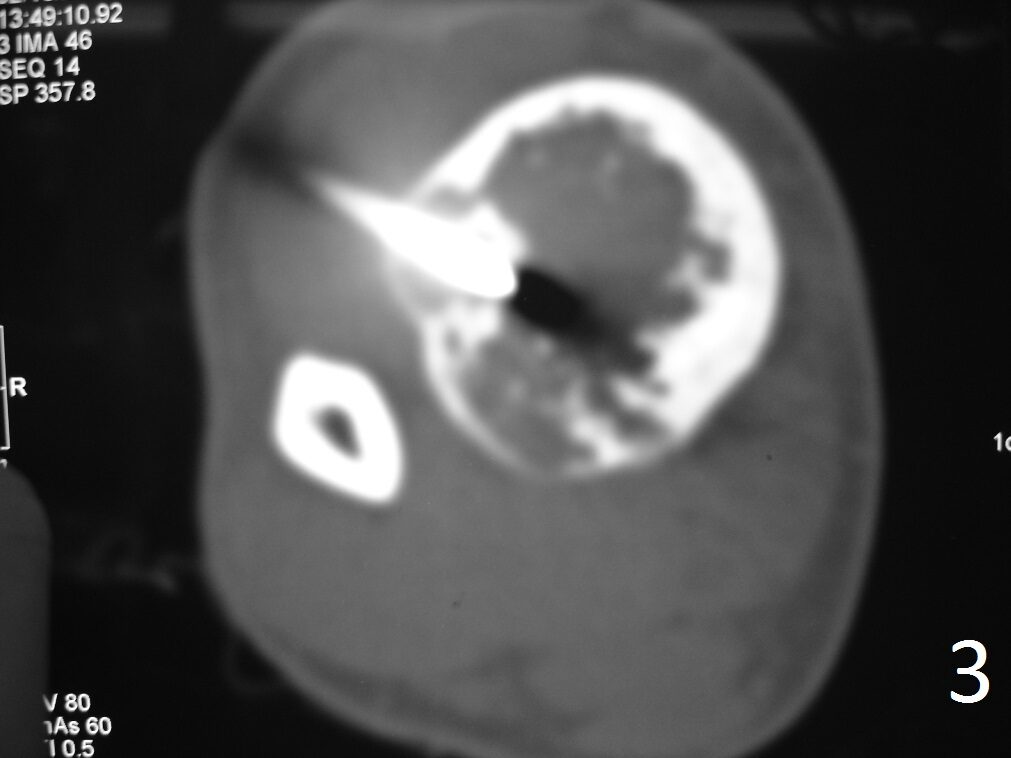

CT (Fig. 3)

• Useful to demonstrate cortical destruction

Fig. 3: Axial CT reconstruction of lower extremity, shows a lytic lesion with posterior cortical destruction during CT guided biopsy.